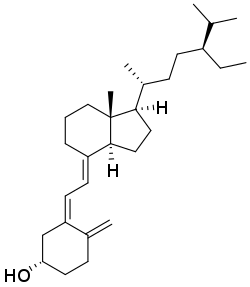

| Vitamin D3 | cholecalciferol

(made from 7-dehydrocholesterol in the skin). |

Several forms (vitamers) of vitamin D exist, with the two major forms being vitamin D2 or ergocalciferol, and vitamin D3 or cholecalciferol.[1] The common-use term "vitamin D" refers to both D2 and D3, which were chemically characterized, respectively, in 1931 and 1935. Vitamin D3 was shown to result from the ultraviolet irradiation of 7-dehydrocholesterol. Although a chemical nomenclature for vitamin D forms was recommended in 1981,[13] alternative names remain commonly used.[3]

Chemically, the various forms of vitamin D are secosteroids, meaning that one of the bonds in the steroid rings is broken.[14] The structural difference between vitamin D2 and vitamin D3 lies in the side chain: vitamin D2 has a double bond between carbons 22 and 23, and a methyl group on carbon 24. Vitamin D analogues have also been synthesized.[3]